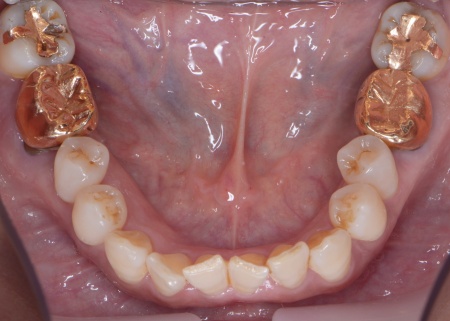

下左右の第1大臼歯を抜歯し、その部位にインプラントを埋め込む手術を行いました。同時に、インプラントの隣にある下の第2大臼歯に対して歯周組織再生療法を施しています。

さらにインプラントの周囲には角化歯肉移植を行いました。これは患者様のお口の中から歯ぐきを採取して移植する方法で、汚れが溜まりにくく清掃しやすい歯ぐきの状態をつくります。

上左右の奥歯についても歯周組織再生療法を行い、歯をできるだけ残せるよう治療を進めました。

また、左上の奥歯は虫歯を取り除いたあと、歯の形を整えて型取りを行い、最終的にジルコニアクラウンを装着しています。

段階的に治療を進め、すべての治療を終了しました。

歯周組織再生療法4ヶ所、インプラント2本、角化歯肉移植、ジルコニアクラウン